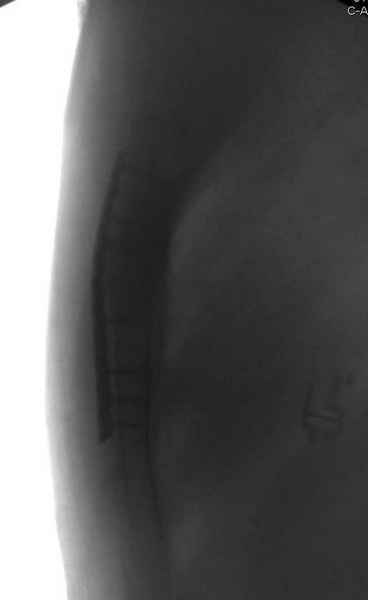

Юра, интересно, насколько такой остеосинтез контролирует степень репозиции, а то у меня имеются снимки девочки 11 лет, направленной ко мне на консультацию из одной из республик бывшего союза.

После торакальной операции, по-видимому, сильно натянули проволоку, и в результате получился захлест отломков в друг друга.

Оперировавший хирург предлагает подождать, а родителей беспокоит проблема прогрессирующей ассиметрии лица, как при кривошее.

С такими продольными несращениями мне не приходилось иметь дело, поэтому направил в один из центральных институтов детской ортопедии России.

А простые посттравматические ложные суставы грудины приходилось оперировать с ограничителем сверла и с фиксацией 2.4 мм пластинами с угловой стабильностью.